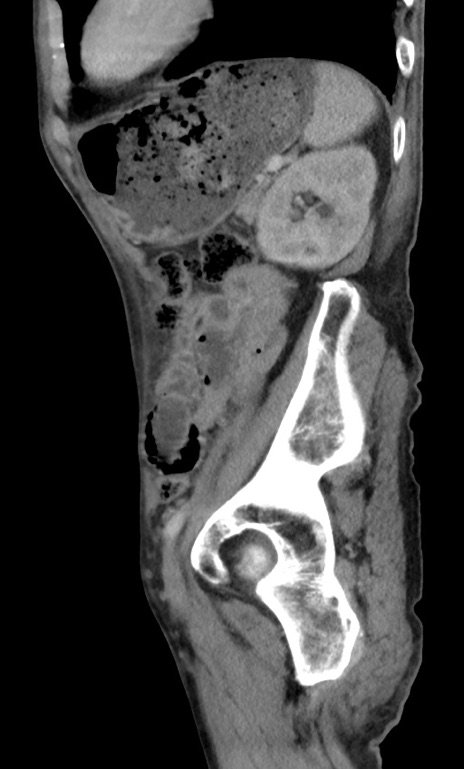

症例3(矢状断像)

【症例】 70歳代男性

【主訴】右鼠径部腫瘤、疼痛

【現病歴】本日朝より上記主訴あり、受診。

【既往歴】膀胱癌にて膀胱全摘、両側尿管皮膚瘻

【データ】WBC 5600、CRP 0.56

冠状断像